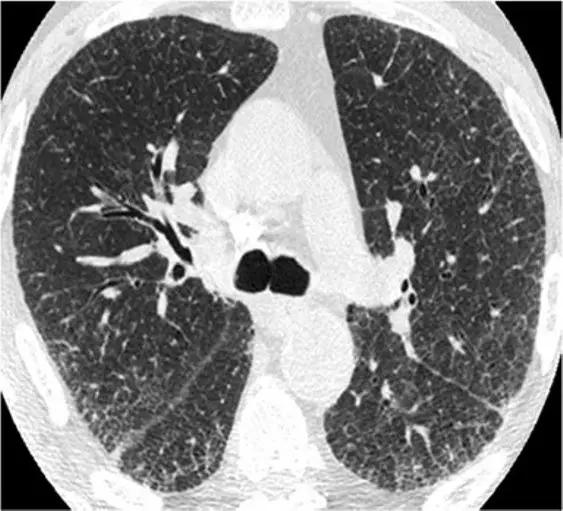

特发性肺纤维化(IPF)有时可能与NSIP难以区分,HRCT在区分IPF和NSIP方面的特异性范围为63%至70%。有利于IPF的鉴别诊断是呈现显著的网状蜂窝样改变,少许毛玻璃改变。

*IPF HRCT在肺底水平上表现出混合的“磨玻璃样和网状图案”,其特征是磨玻璃样改变的区域内可见牵引性支气管扩张和支气管扩张。少许蜂窝样改变。